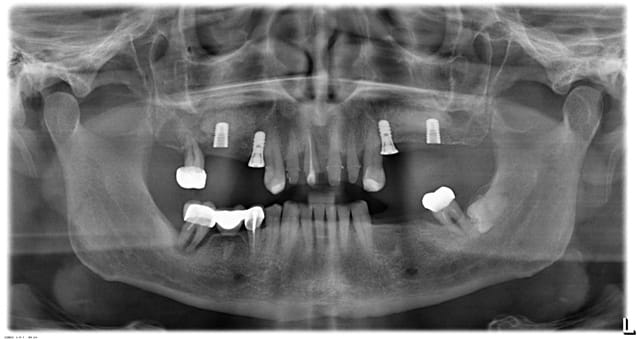

je précise que la réhabilitation du secteur ant est faite dans le cadre d'une reconstruction globale, ci joint la derniere radio et projet proth.

Capture ley5kt - Eugenol

Goarrin j 20120515 785 nfxhtp - Eugenol